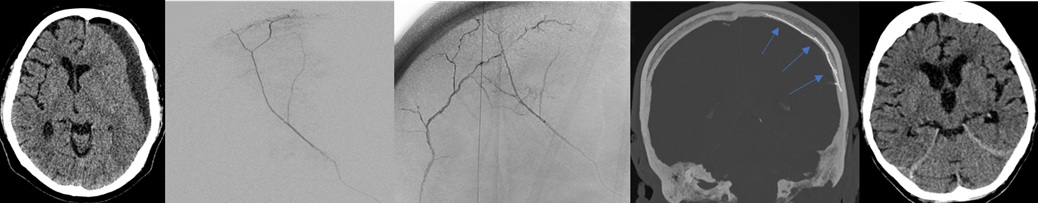

Neue Perspektiven bei subduralem Hämatom: MMA-Embolisation erweitert das Radiologie-Angebot

15. Januar 2025 - Das Institut für Radiologie und Neuroradiologie erweitert ihr Leistungsportfolio um eine moderne, minimalinvasive Therapieoption, die als Ergänzung zur operativen Behandlung den Krankheitsverlauf bei Patienten mit Subduralhämatom positiv beeinflussen kann. Weiterlesen